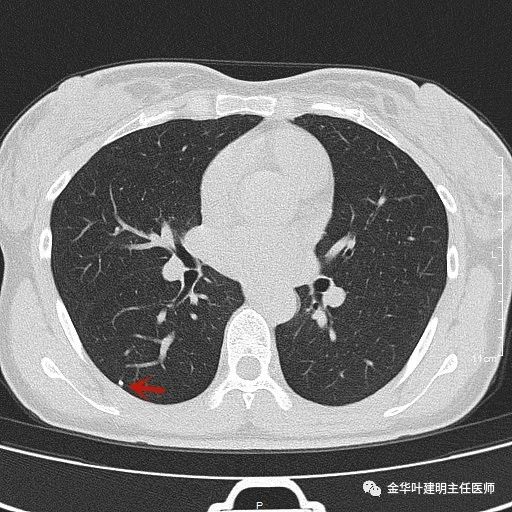

上图示慢性炎结节。我们见其桔色箭头示长毛刺征,绿色箭头示有血管贴边,但进出病灶的血管粗细相对没有什么改变(说明没有被病灶窃取多少血供),整体病灶边缘偏模糊。